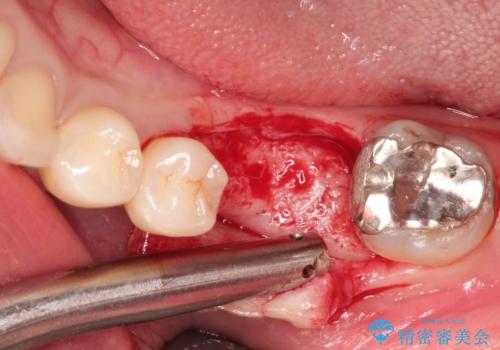

- Ⅲ度の分岐部病変をきたした第1大臼歯を抜去、待時しインプラントによる咬合回復を計画した。

奥歯の根の又の部分の歯周病(=分岐部病変)が進行してしまった場合、

・掃除をしながら様子をみる

・歯の形態を修正し清掃性の向上をはからう

・歯を分割し小臼歯形態×2で補綴する(確定外科が必要)

・より病変の影響を強く受けている方の根だけ抜去し、残った根を温存する

など多様な治療の選択肢があります。

ケースによりますが、いずれの場合も不安要素をかかえたまま歯を温存することになるため、それらを取り除く・かつ感染源を取り除くために歯を抜去するのも効果的な治療法といえます。